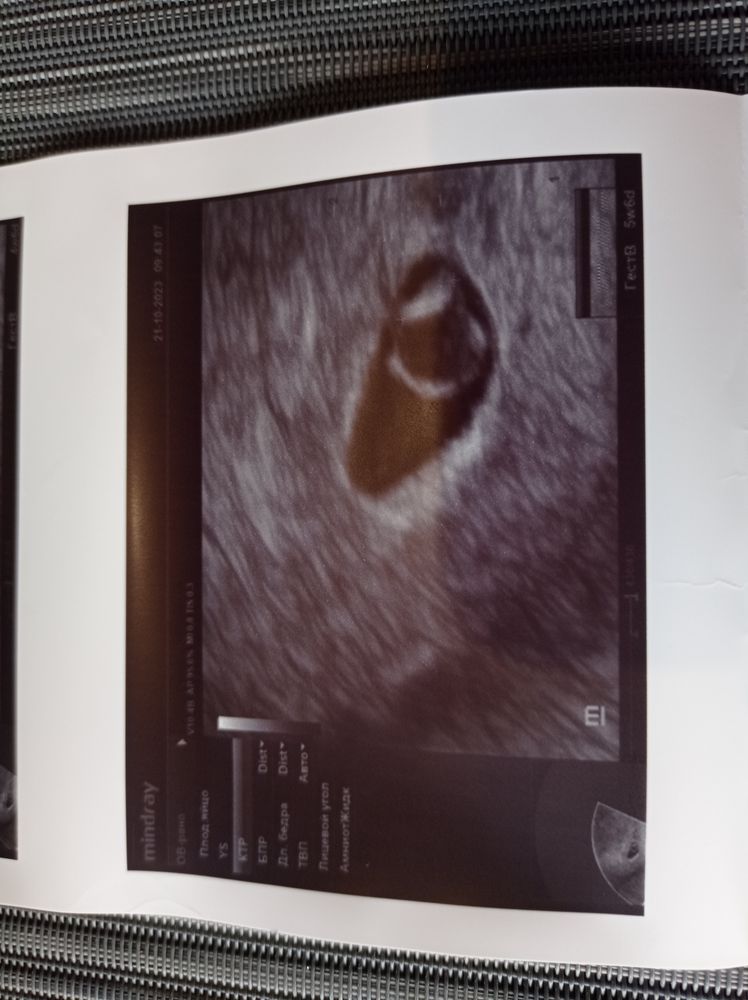

Наше знакомство с малышом - первое узи

УЗИ, КТГ, доплерСегодня 5 недель и 6 дней, дотерпела я до первого УЗИ. Всё у нас отлично, есть эмбриончик ктр 2.8 мм, пя 11.2 мм, видно как бьётся сердечко! Следующее УЗИ через неделю, уже у гинеколога, у которого я скорее всего буду вести беременность.